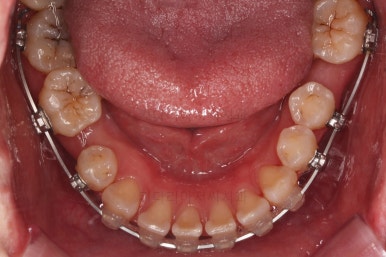

치열이 매우 가지런해졌고, 아래 앞니 사이 틈새도 점점 오므려져 가고 있습니다.

발치 공간을 적극적으로 줄여 나갑니다.

이 과정에서 입매, 앞니 각도, 정중선 등을 신경 써줍니다.

아무래도 상하좌우 비어 있는 공간의 위치가 모두 달랐기 때문에 자칫하면 중앙선이 한 쪽으로 쏠려버릴 수 있기 때문이죠.

발치 공간도 많이 줄었네요.